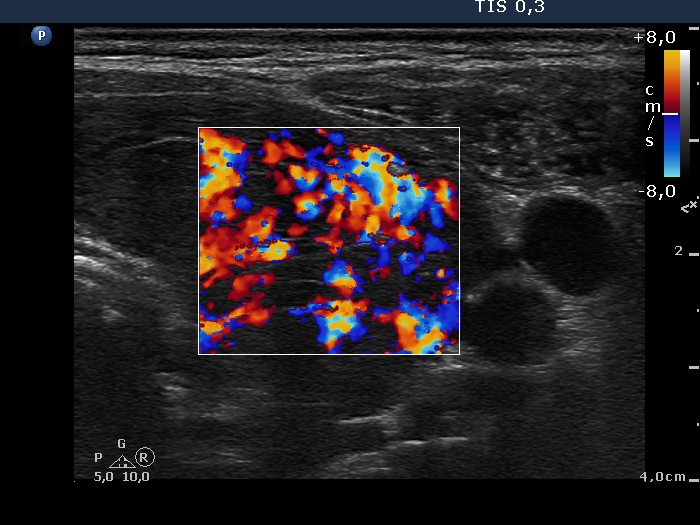

Consecutively operated patients with autoimmune thyroid disease - case 15 (679) (ultrasonographic picture 6)

Left lobe, transverse view, color Doppler mode. The vascularization is extremely increased.